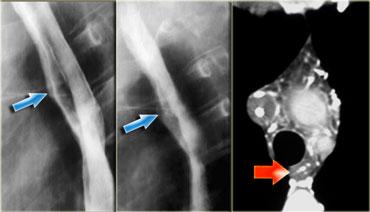

Bên trái là hình chụp thực quản cản quang của bệnh nhân có quai động mạch chủ phải tạo ra ấn lõm phía sau trên hình chiếu nghiêng (mũi tên xanh dương).

Quai động mạch chủ đôi – TRÁI: Quai phải và quai trái ấn lõm thực quản (mũi tên) ở các mức độ khác nhau – PHẢI: Hình chụp mạch máu với quai đôi ở bệnh nhân 65 tuổi không có triệu chứng

Bên trái là một trường hợp quai động mạch chủ đôi khác.

Phim X-quang ngực cho thấy đông đặc phổi phải do hít sặc ở trẻ 6 tuổi.

Quai phải và quai trái ấn lõm thực quản (mũi tên) ở các mức độ khác nhau.

Động mạch phổi trái bất thường: động mạch bất thường chạy giữa khí quản và thực quản, ấn lõm cả hai cấu trúc (mũi tên)

Động mạch phổi trái bất thường ấn lõm mặt sau khí quản và mặt trước thực quản khi chạy giữa hai cấu trúc này.

Hẹp phế quản phải có thể gây ứ khí hoặc xẹp phổi.